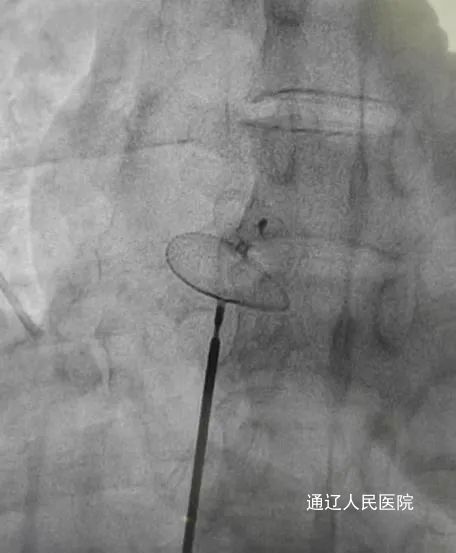

在心脑血管专家的会诊下,最终诊断为先天性心脏病-卵圆孔未闭。考虑该孔道是患者心梗、脑梗的罪魁祸首,在与患者及家属充分沟通后,决定于3月3日进行卵圆孔未闭封堵手术。手术过程顺利,仅用时20分钟便完成了手术,成功封堵了卵圆孔。在心内科医护团队的精心护理下,患者术后恢复良好,心脑疾病的威胁得到了有效控制。